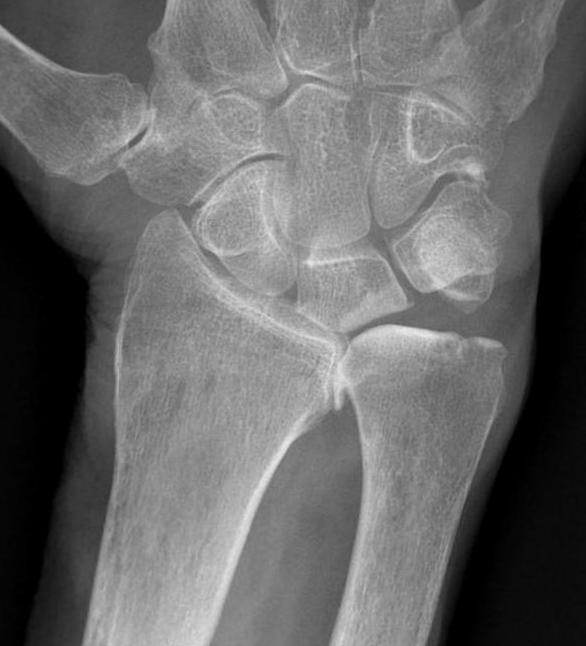

Xray

DRUJ instability

Post traumatic distal ulna osteoarthritis